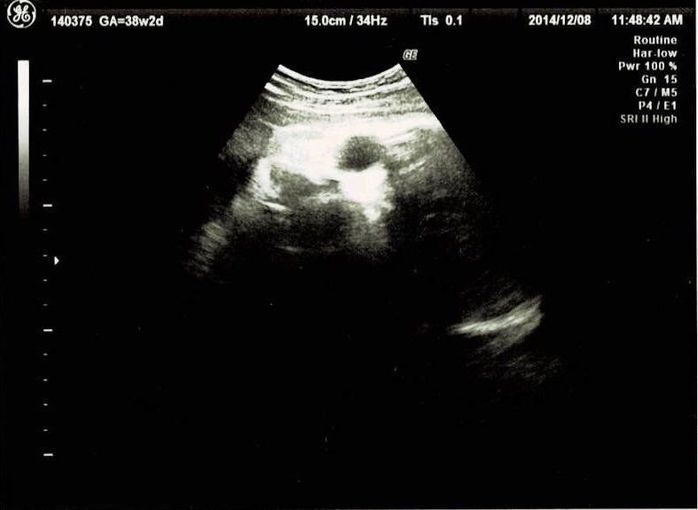

妊娠38週目エコー写真 出産直前! マイナートラブル頻発

いよいよ生まれそうです。この頃は、急に陰部のかゆみが出たり、陣痛のような痛みがずっと続いたりと、体の変化で毎日気を張っていました。陣痛のような痛みをアプリで計測し、結果を印刷して先生に見せたところ、もうお産が始まっていても良い間隔だと言われました。それでも動きが弱すぎて、実際に生まれるまでさらに一週間かかりました。